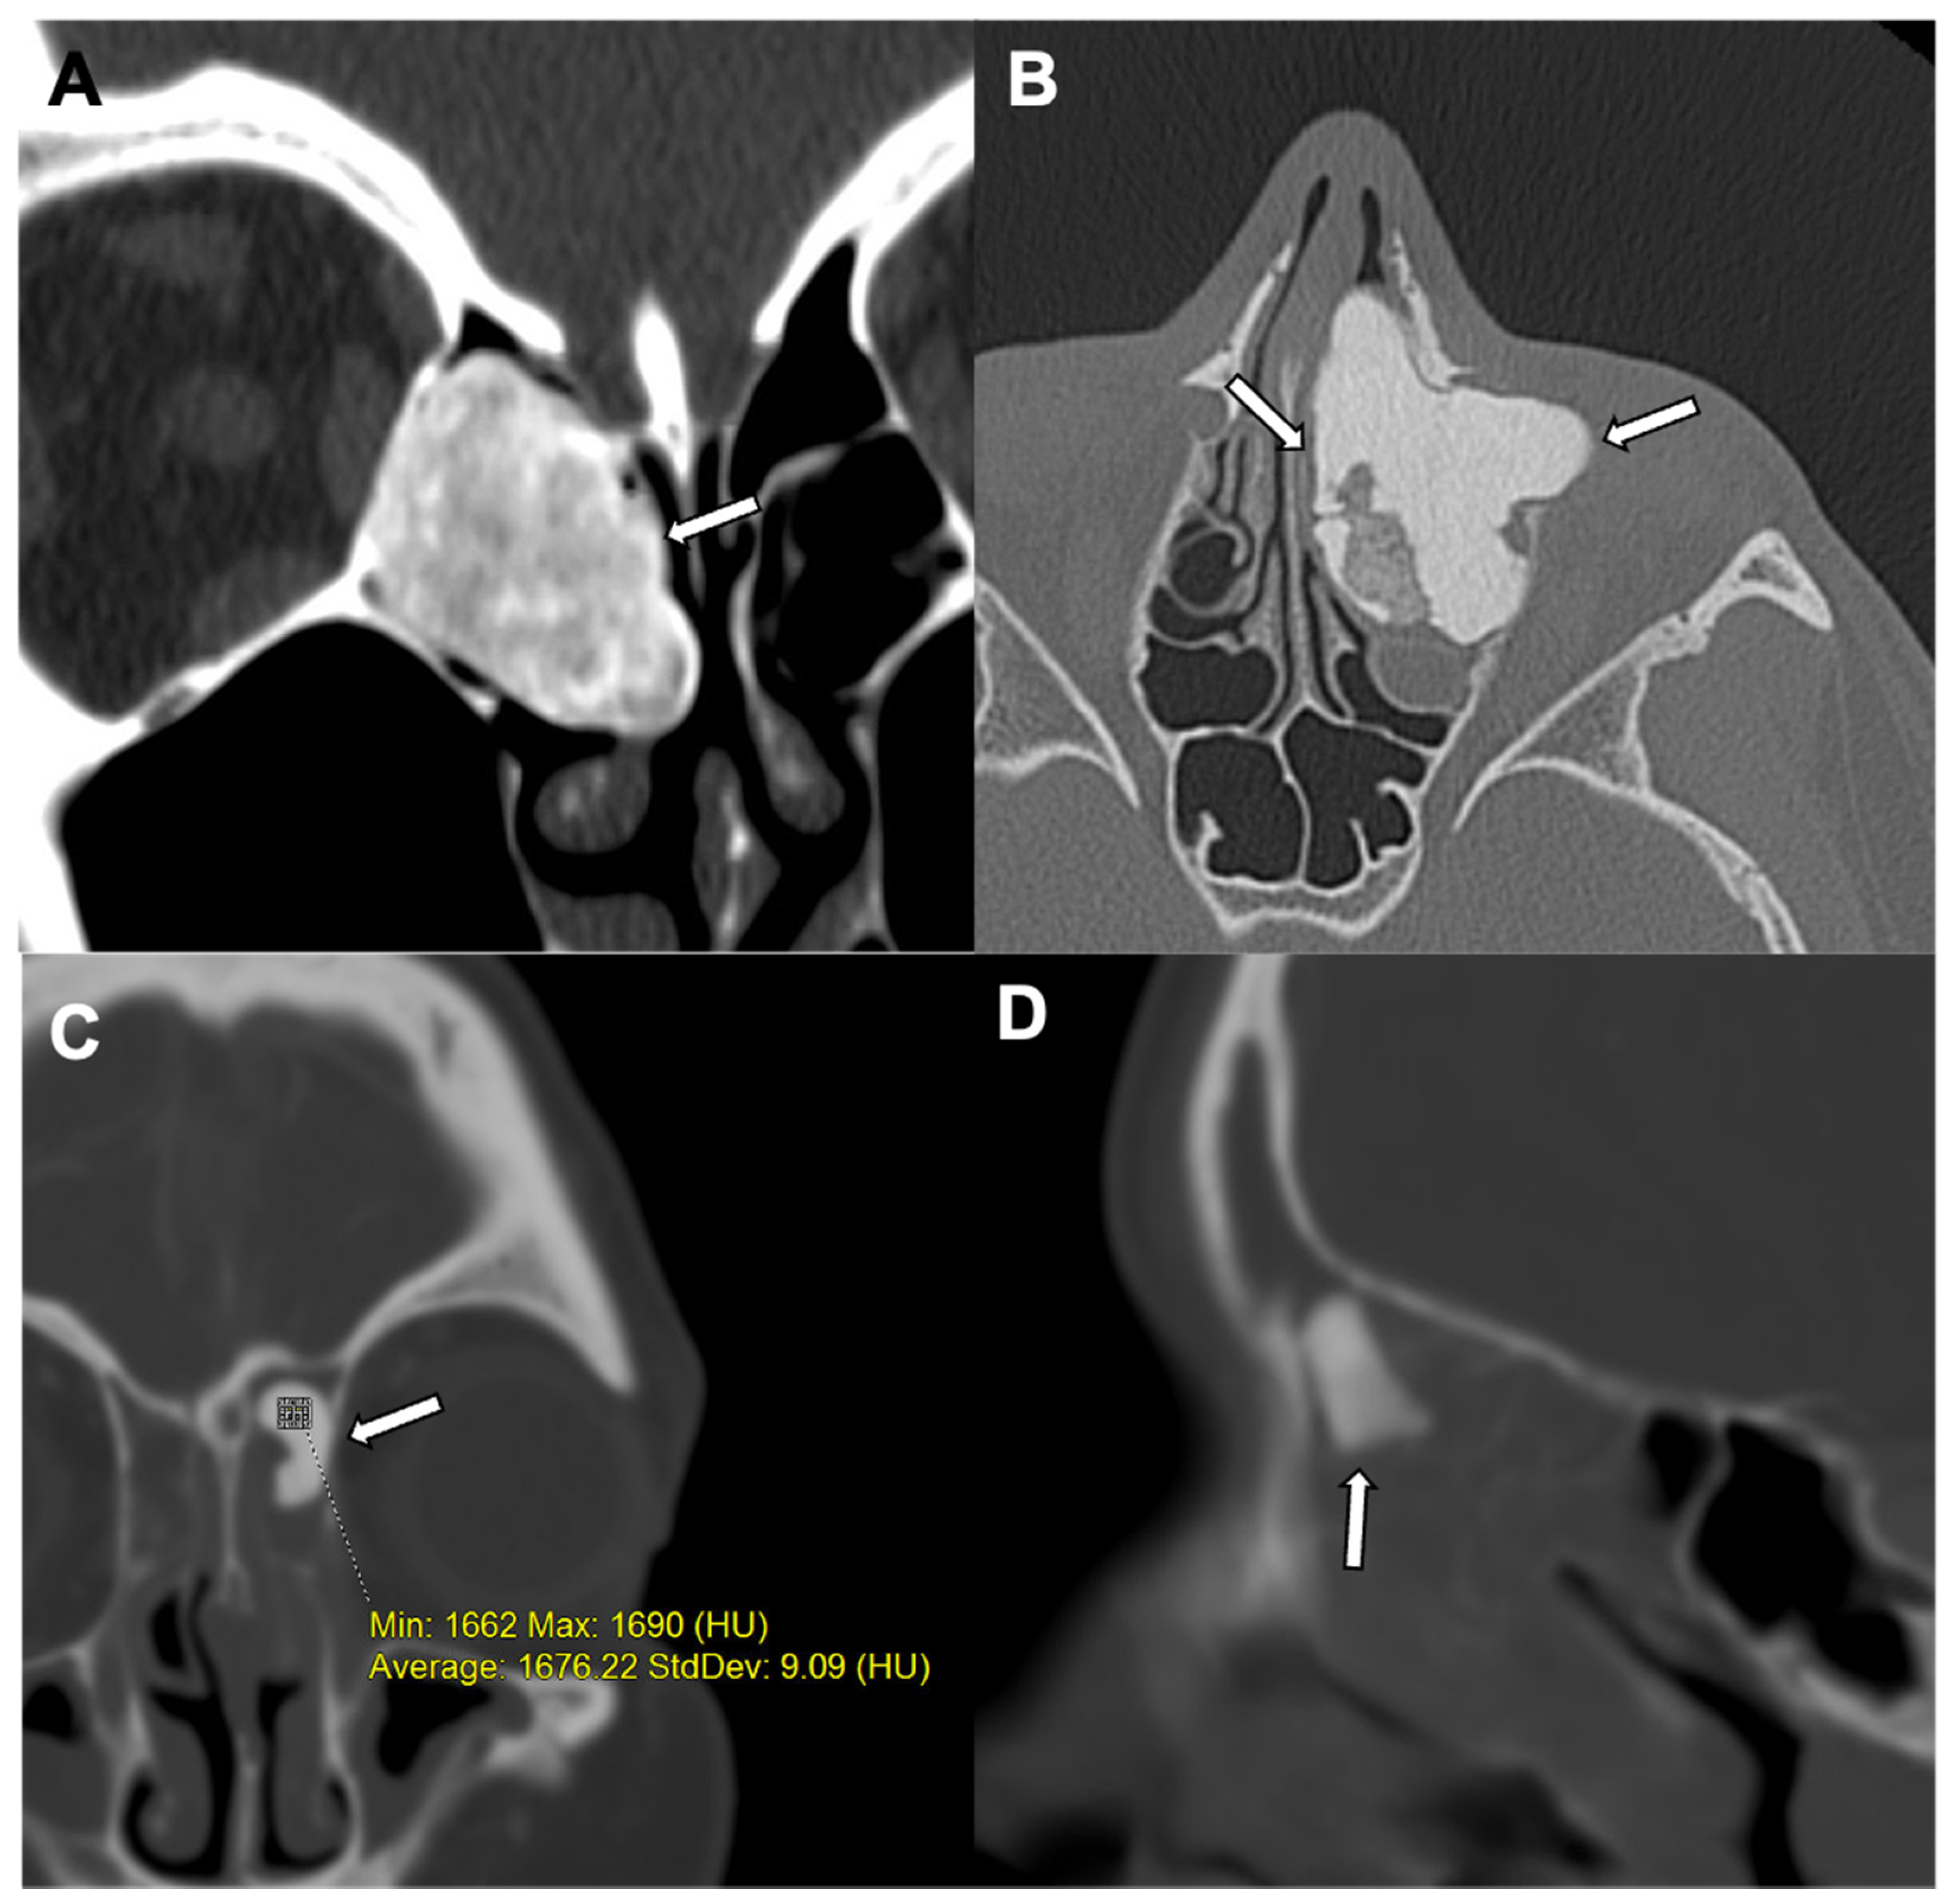

3. Osteoma

- Ivory osteoma (also known as eburnated osteoma) contains dense bone without a haversian system.

- Mature osteoma (also known as osteoma spongiosum) is histologically similar to normal bone. Mature osteoma is composed of trabecular bone, often with marrow.

- Mixed osteoma contains features of both ivory and mature osteoma.

| Radiographic/CT features | Juxtacortical, well-circumscribed homogenous sclerotic lesion | Homogenous intra-medullary sclerotic focus with spiculated margins | Small (less than 2 cm) cortical lucency with extensive surrounding sclerosis | Expansile large (more than 2 cm) lucent lesion with matrix mineralization |

| Treatment | None if asymptomatic; excision if complications related to mass effect | None | Percutaneous CT guided radiofrequency ablation | Surgery or percutaneous CT guided ablation |